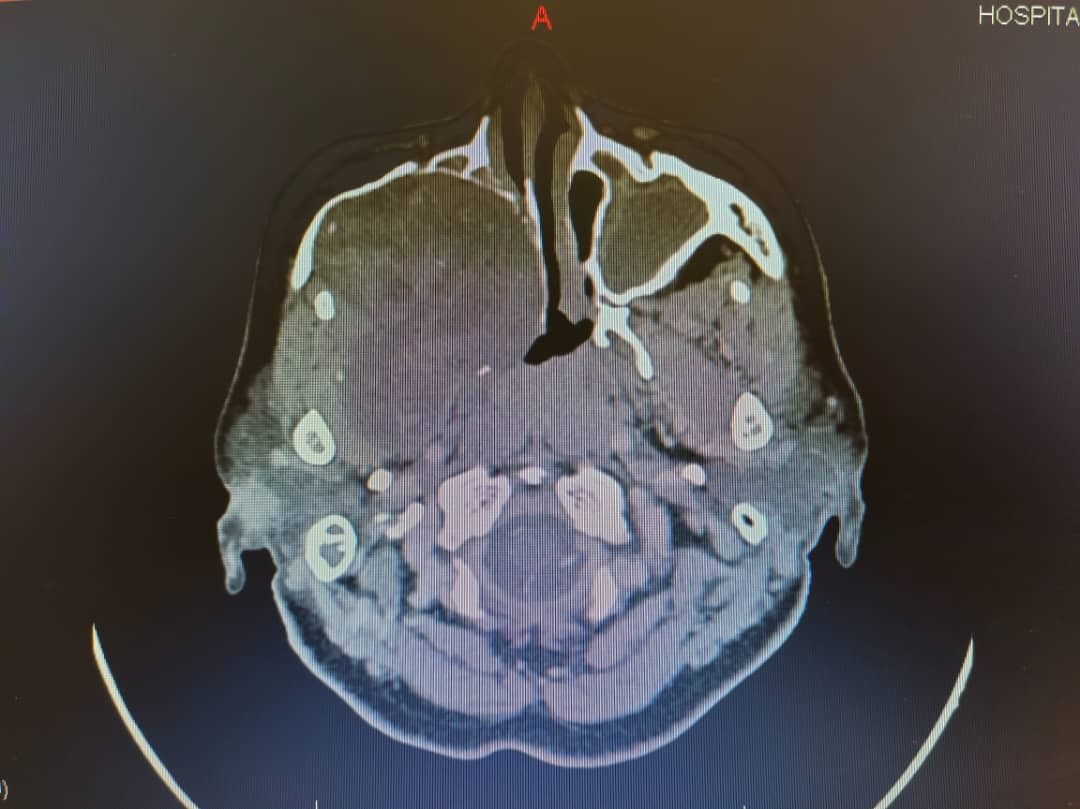

Schwannomas, also known as neurilemmomas, are benign nerve sheath tumors originating from Schwann cells of the peripheral nervous system. Sinonasal schwannomas are rare, comprising approximately 4% of all schwannomas. These tumors are typically slow growing, often leading to delayed clinical presentation. Despite their benign nature, their indolent progression can result in significant morbidity due to mass effect on adjacent vital structures. We report a case of a large, late-diagnosed right sinonasal ancient schwannoma causing extensive compression of surrounding tissues, including the right frontal and temporal lobes, ultimately resulting in vision loss due to compressive optic neuropathy. Ocular symptoms may be the initial manifestation of sinonasal tumors and should raise concern for potentially aggressive lesions. Prompt recognition and early referral are critical to minimize complications and improve patient outcomes.